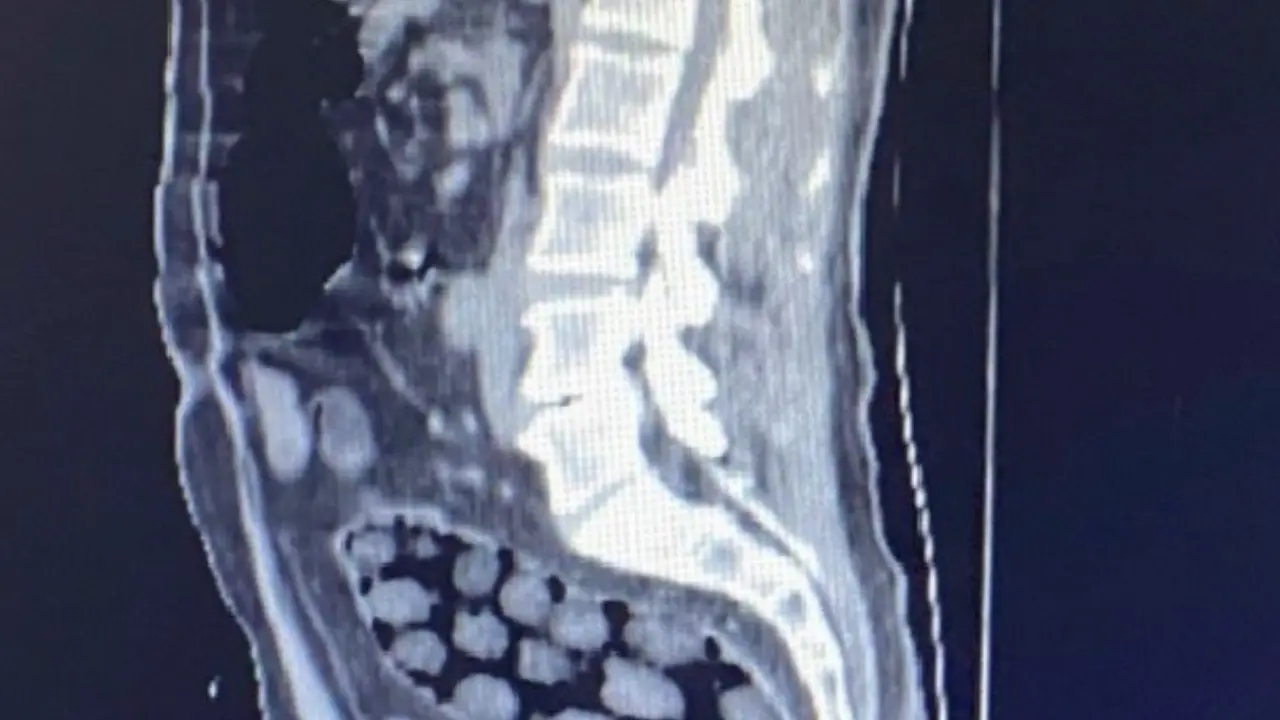

Şüpheliler, Tatvan Devlet Hastanesi’ne sevk edilerek, detaylı tıbbi muayeneye alındı. Yapılan röntgen ve tomografi taramalarında, mide ve bağırsaklarda toplamda 91 adet paket olduğu görüldü. Şüpheliler, bu paketleri yutmuştu. Tıbbi müdahaleyle söz konusu paketler çıkarıldı ve içeriklerinin 1 kilogram 126 gram metamfetamin maddesi olduğu belirlendi.